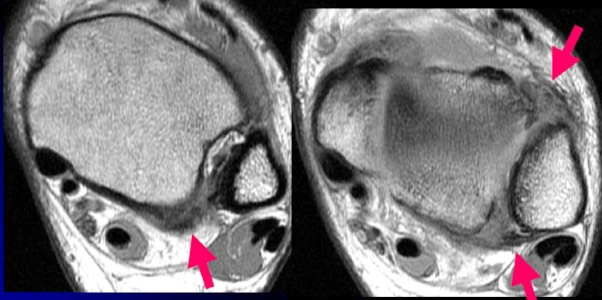

MRI of ankle syndesmosis injury. Arrows show AITFL and PITFL injury damage

If plain x-rays are inconclusive, an MRI or CT should be performed. MRI scans are more effective in soft tissue injury, while CT is more effective when looking for bony injury (Porter 2014).